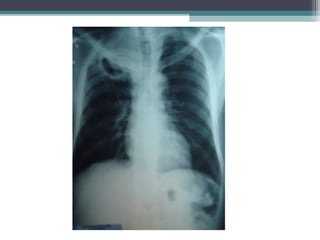

• Rx do Tórax (29/06/12)

EXAMES COMPLEMENTARES • Rxdo Tórax (29/06/12) ▫ Redução da transparência em terço superior do pulmão direito com cavidade de parede espessa em permeio. Avaliar processo granulomatoso em atividade. ▫ Seios costo frênicos livres e coração e vasos da base sem alterações.

Tumor de Pancoast •Avaliação radiológica ▫ Rx do tórax:  Opacidade apical > 5mm  Destruição óssea